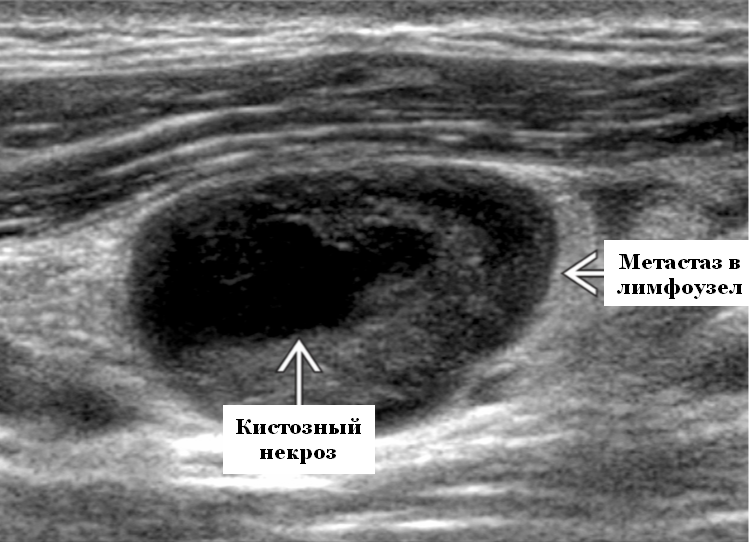

3. Неоднородная структура

В норме лимфоузел имеет однородную структуру с хорошо различимыми корковым и мозговым слоем. Появление темных очагов (участков некроза) или светлых (кальцинатов) может указывать на метастазы или лимфому.

Лимфоузел пораженный метастазом